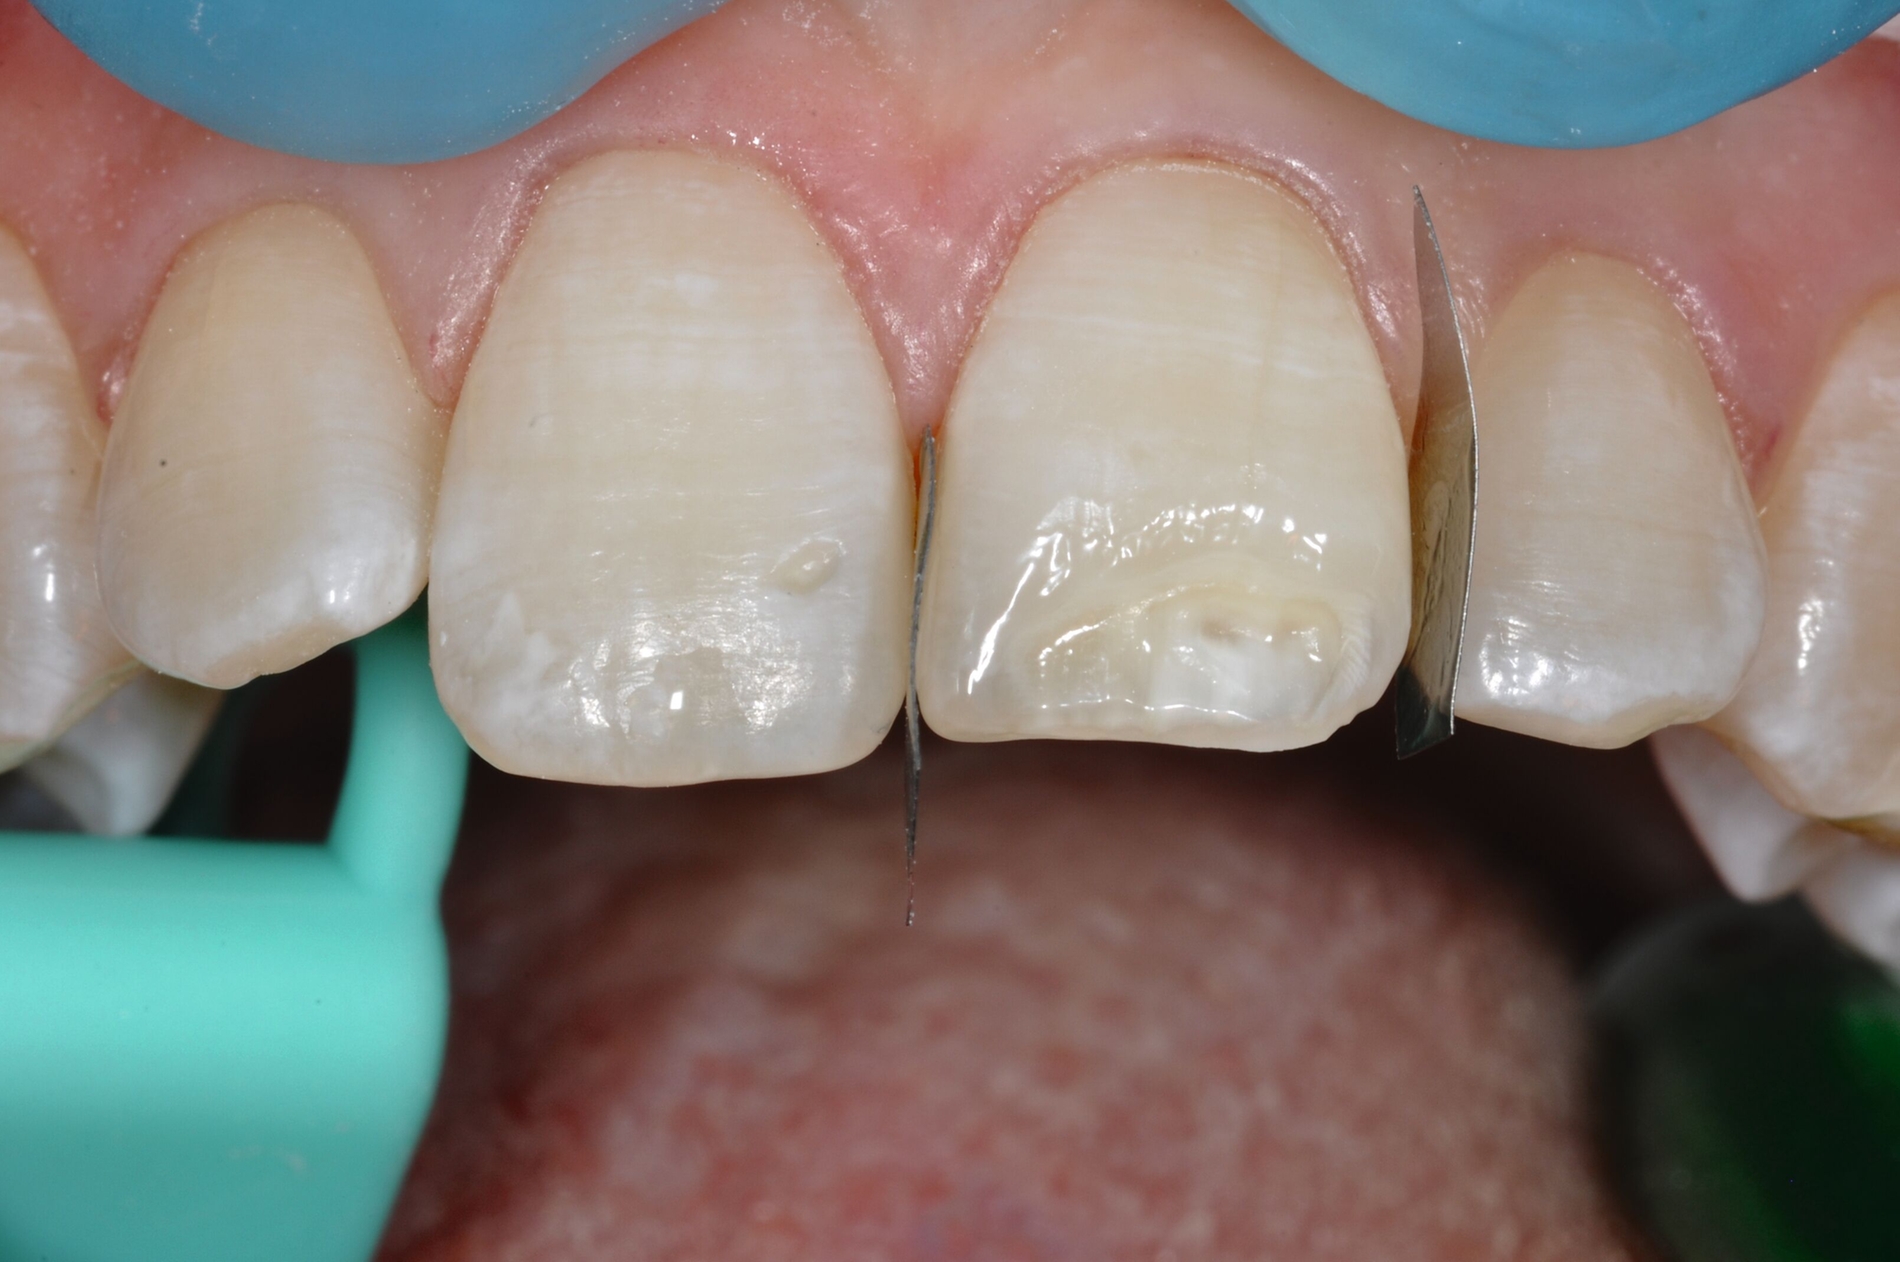

Während die Dentinhaftung unterhalb des affektierten Schmelzes vergleichbar mit der von gesundem Dentin ist, funktioniert die Haftung an dem strukturell veränderten Schmelz schlechter. Eigene Untersuchungen haben gezeigt, dass die Haftung an dem porösen, proteinreichen Schmelz stark reduziert ist (Abbildung 8) [Krämer et al., 2018]. Sind die Füllungsränder in dem veränderten Bereich lokalisiert, muss mit Randspalten und Abplatzungen gerechnet werden.

Die Versorgung der MIH-Frontzähne entspricht dem Vorgehen im Seitenzahnbereich. Problematisch ist die Maskierung der Opazitäten. Dazu müssen opake Komposite verwendet werden und es muss eine Schichtstärke von circa 1,5 mm garantiert sein (Abbildung 9).